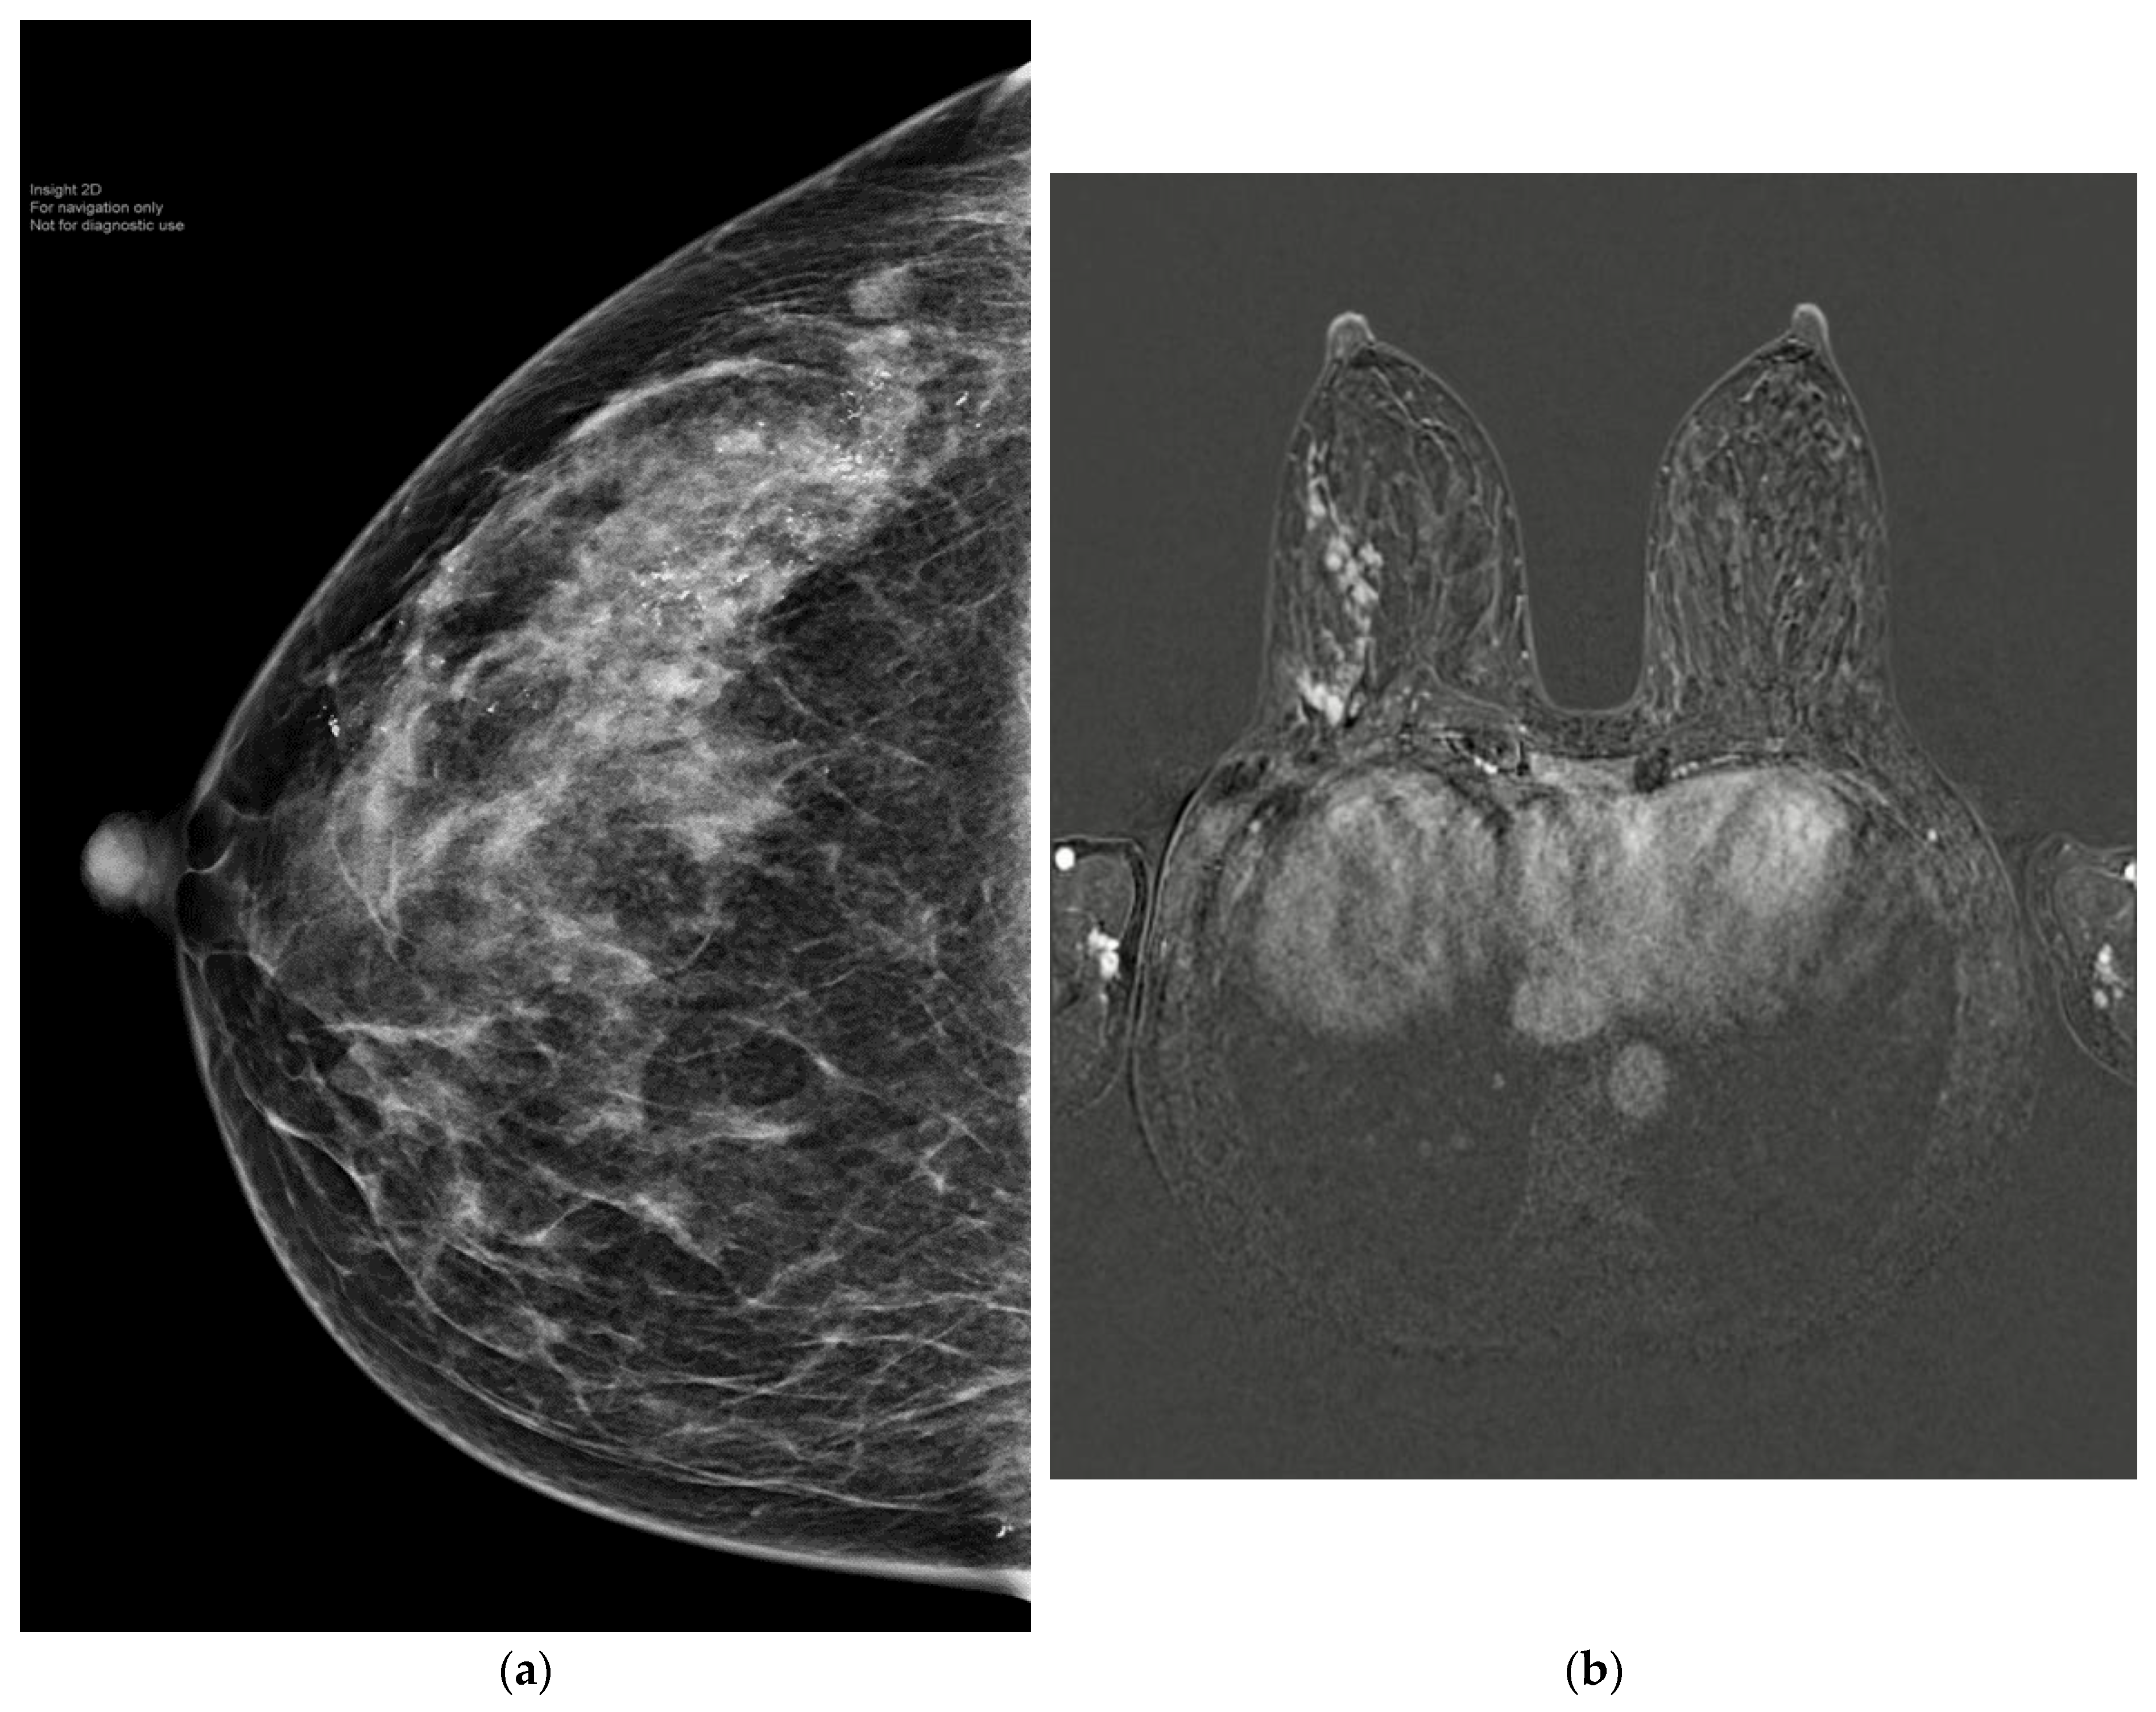

- Fowler, A.M.; Mankoff, D.A.; Joe, B.N. Imaging Neoadjuvant Therapy Response in Breast Cancer. Radiology 2017, 285, 358–375. [Google Scholar] [CrossRef]

- Yuan, Y.; Chen, X.S.; Liu, S.Y.; Shen, K.W. Accuracy of MRI in prediction of pathologic complete remission in breast cancer after preoperative therapy: A meta-analysis. AJR Am. J. Roentgenol. 2010, 195, 260–268. [Google Scholar] [CrossRef]

- Expert Panel on Breast, I.; Slanetz, P.J.; Moy, L.; Baron, P.; diFlorio, R.M.; Green, E.D.; Heller, S.L.; Holbrook, A.I.; Lee, S.J.; Lewin, A.A.; et al. ACR Appropriateness Criteria((R)) Monitoring Response to Neoadjuvant Systemic Therapy for Breast Cancer. J. Am. Coll. Radiol. 2017, 14, S462–S475. [Google Scholar] [CrossRef]

- Kuerer, H.M.; Rauch, G.M.; Krishnamurthy, S.; Adrada, B.E.; Caudle, A.S.; DeSnyder, S.M.; Black, D.M.; Santiago, L.; Hobbs, B.P.; Lucci, A., Jr.; et al. A Clinical Feasibility Trial for Identification of Exceptional Responders in Whom Breast Cancer Surgery Can Be Eliminated Following Neoadjuvant Systemic Therapy. Ann. Surg. 2018, 267, 946–951. [Google Scholar] [CrossRef] [PubMed]